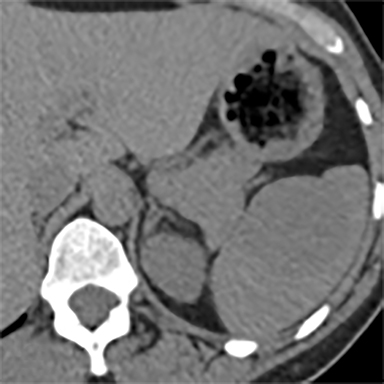

En algunas enfermedades, como la amiloidosis, leucemia, linfoma, síndromes mieloproliferativos, quistes y tumores metastásicos, el bazo puede aumentar de tamaño y causar dolor.